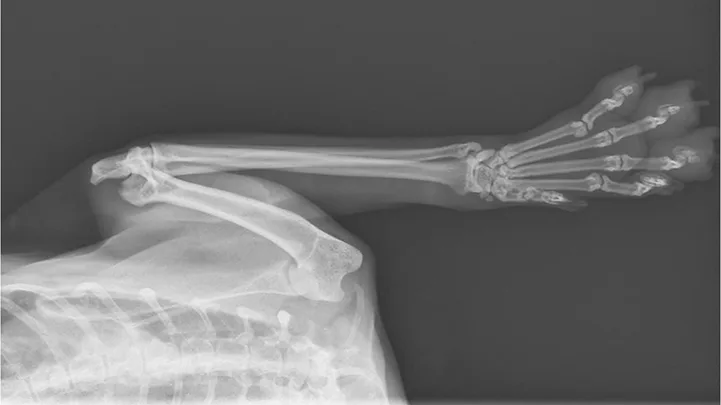

Figure 1

Lateral thoracic radiograph of a 14.5-year-old male domestic cat with a caudal dorsal cavity primary lung mass. Image courtesy of Rachel Moon, DVM, DACVR

Reported primary lung tumors (Figures 1 and 2) include squamous cell carcinoma and sarcoma, but adenocarcinomas are reportedly the most common histopathologic diagnosis.2 Adenocarcinomas are subcharacterized by location (ie, bronchial, bronchioloalveolar, alveolar) and grade. Carcinomas are graded on histopathology as differentiated or undifferentiated, with the grade directly correlating with metastatic incidence.1,3 Although most primary carcinomas are localized and solitary at diagnosis,1,4 the literature suggests that >50% of undifferentiated carcinomas and 90% of squamous cell carcinomas metastasize,1,3 with one study reporting ≈75% of feline lung tumors as metastatic.4 Metastasis to the lungs, skin, CNS, and digits may occur transpleurally, hematogenously, or via lymphatics or airways.1,3,4

Radiographs may reveal extensive osteolysis of the distal phalanx that may cross the joint space. Thoracic radiographs often show a single primary lung mass, although diffuse nodular disease has also been noted.1 No clinical signs of respiratory distress in affected cats have been reported.6